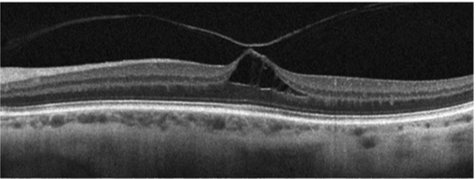

Name the condition

Macular holes

Top one=Still some intact macula tissue

2=Laminar hole

3=Operculum pulled off

4=Parting until bruch’s membrane

Describe the pic

Macular hole

OCT cross section

Vitreous come off but the macula is pulling/still attached

Large cystic space underneath

Pt complaining of reduced central vision/blurriness